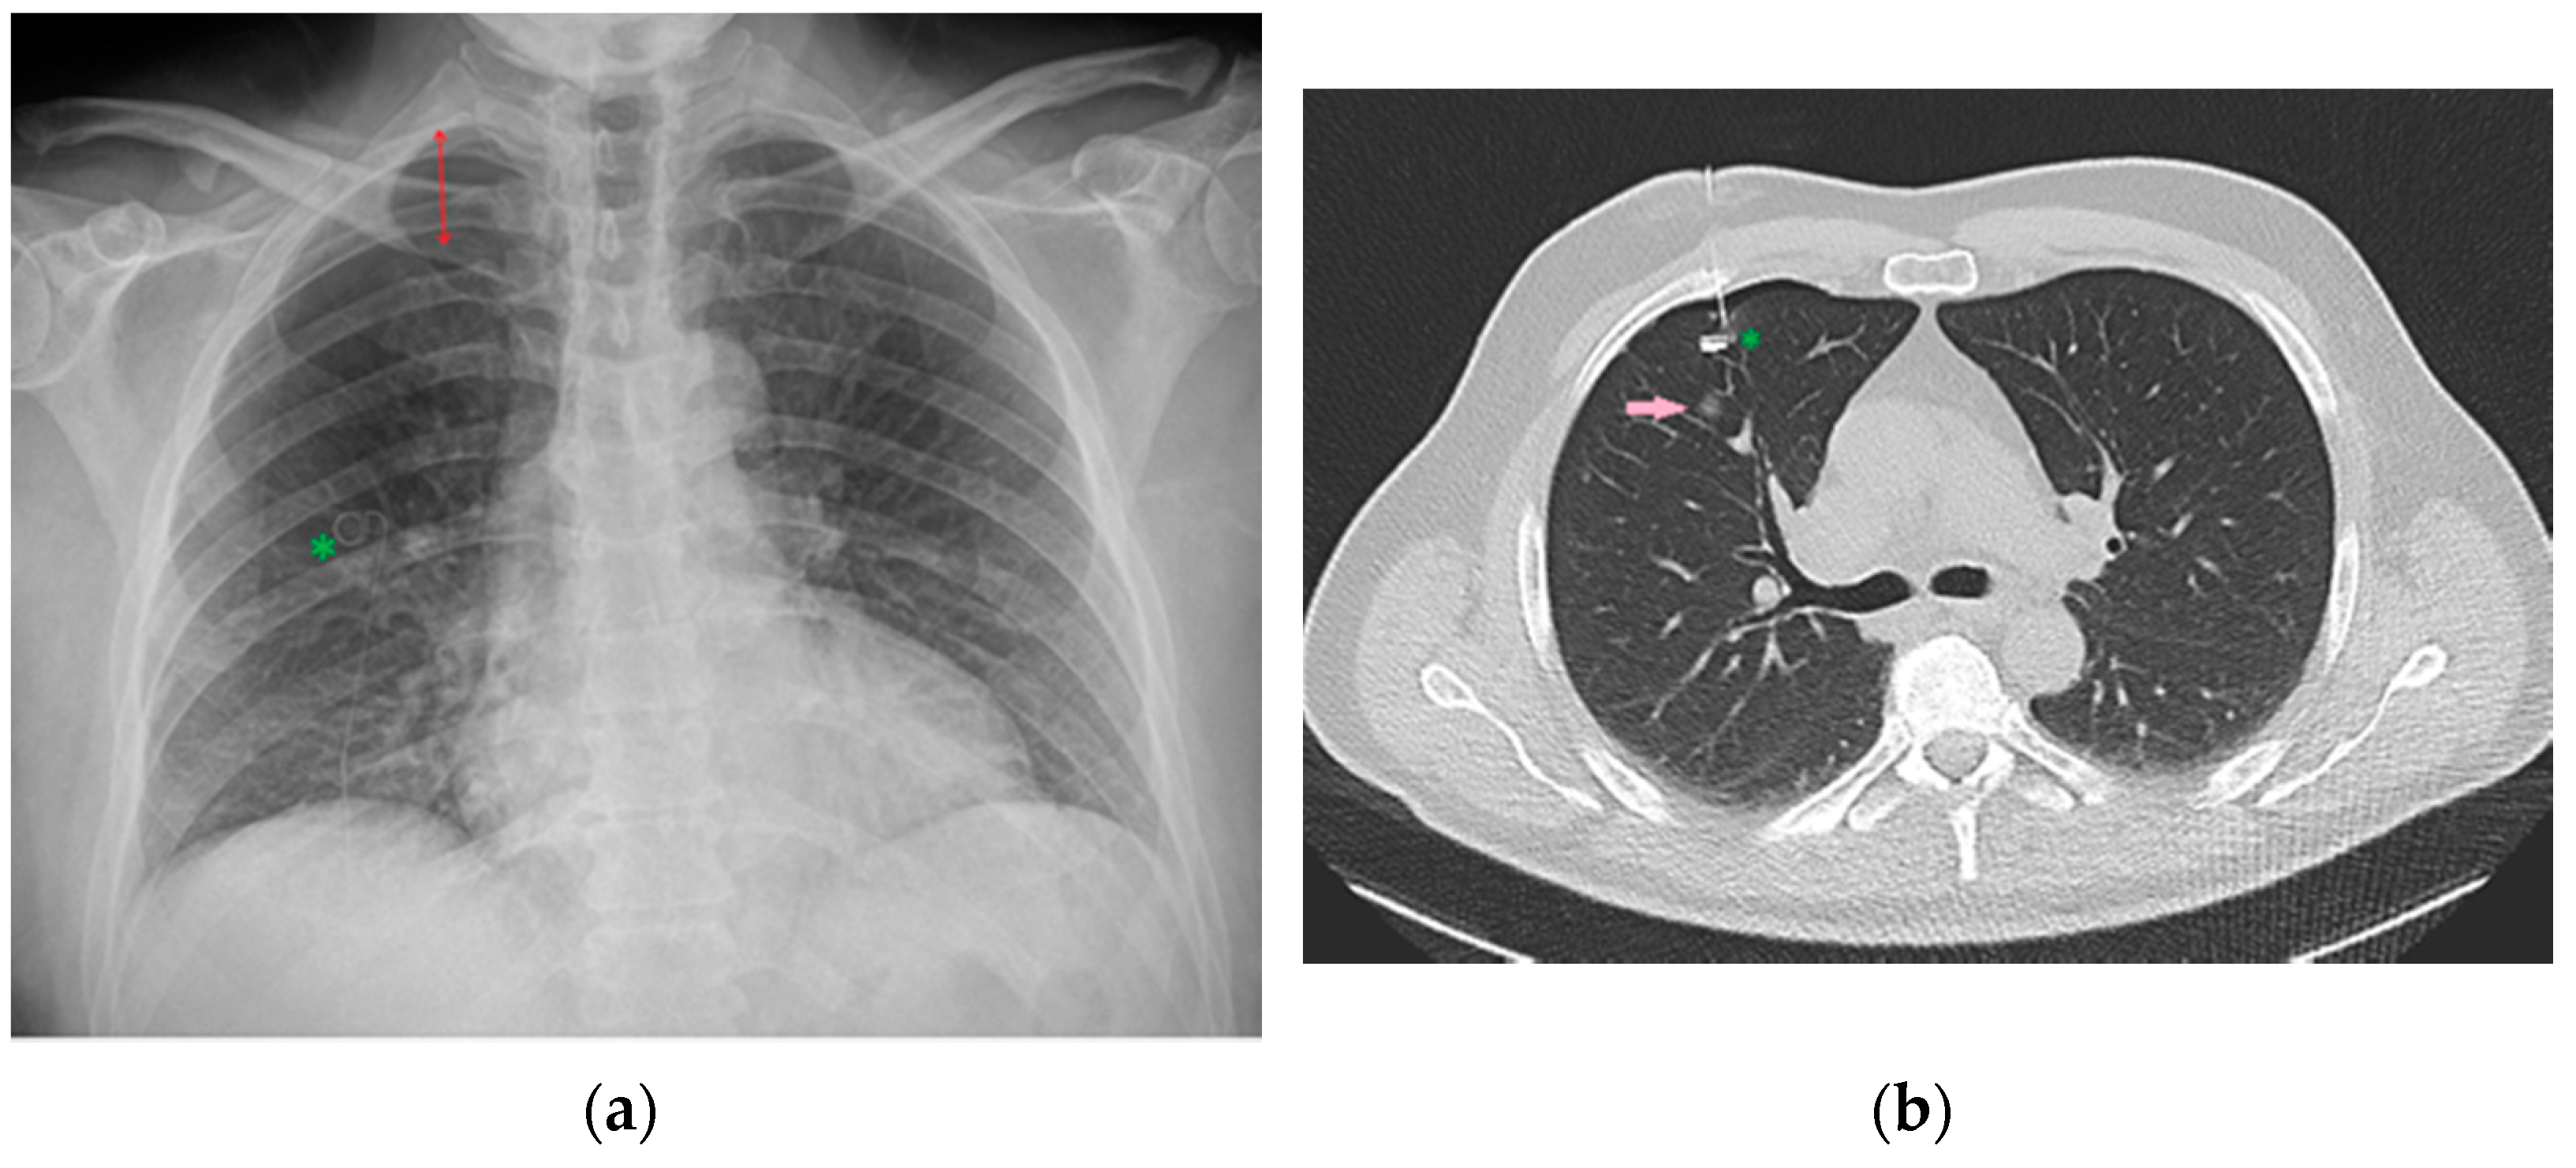

Figure 34.

Image of a CXR (a) obtained after CT-guided positioning (b) of a microcoil (green asterisk) into the lung parenchyma as a landmark to more easily recognize and resect the adjacent nodule (pink arrow) intraoperatively. Development of pneumothorax as a complication following this procedure is not uncommon [36], as it is possible to appreciate this in the reported CXR (red double arrow).